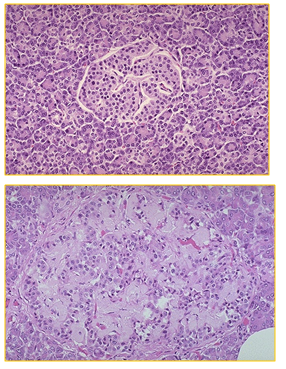

What can be seen here?

One of knock on consequences of DM is amyloid deposition in the pancreas